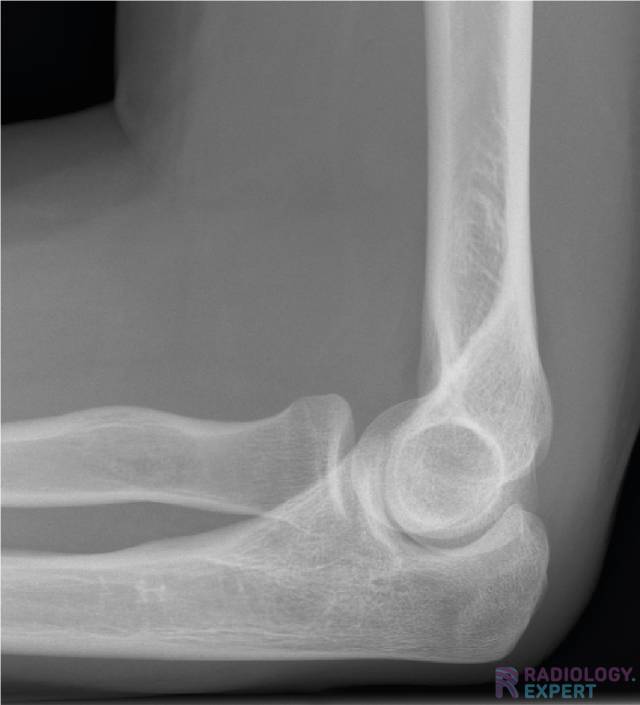

An X-ray of the elbow is a frequently conducted examination and is mainly used for diagnosing a fracture.

Some of the key topics are radial head fracture, supracondylar humeral fracture, anterior/posterior fat pad and elbow luxation.

Normale anatomie op een  X-elleboog opname (laterale opname) Normale anatomie op een  X-elleboog opname (laterale opname)

Click image to see overlay